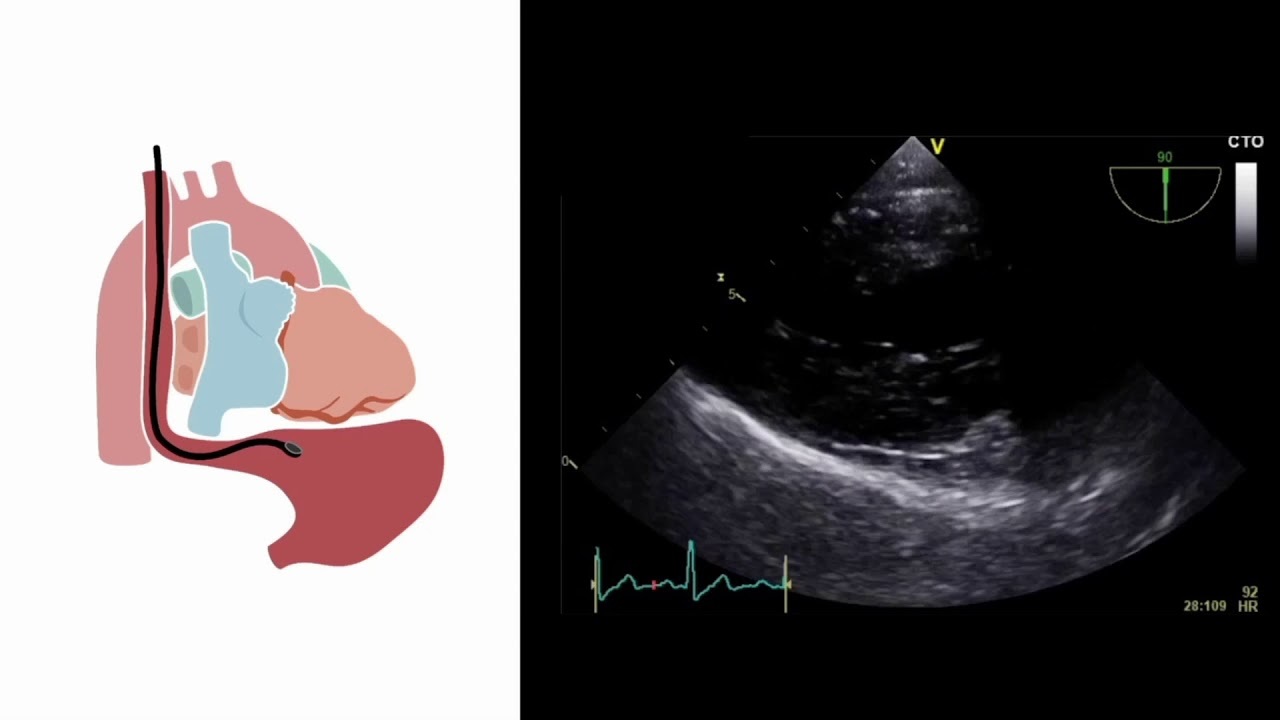

A procedure. A probe inserted in the esophagus/stomach, it takes an ultrasound of the heart.

Transesophageal Echocardiography (TEE)